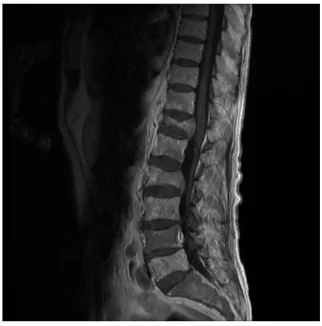

Imagine RMN al unui pacient cu fracturi tasare pe fondul unor metastaze vertebrale ale unui melanom malign.

De asemenea medicul vă poate indica un examen de Rezonanță Magnetică Nucleară (RMN), care facilitează diagnosticul și oferă informații despre vechimea fracturii, despre măduva spinării, elementele nervoase și discurile intervertebrale.